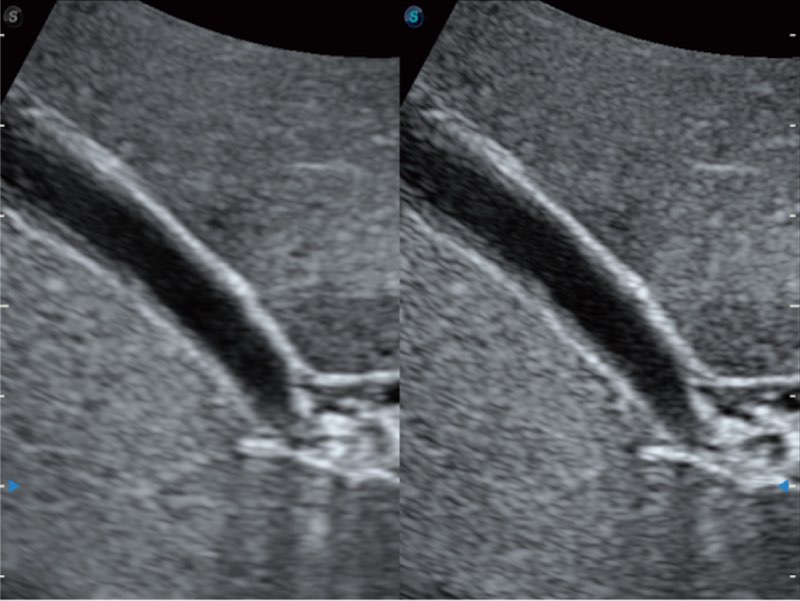

Przy pracach nad aparatem ProPet 60 uwzględniono najważniejsze preferencje i potrzeby weterynarzy, oferując finalnie przystępne cenowo i odpowiednio wyważone połączenie znakomitej precyzji klinicznej, zwiększonej wydajności i przemyślanego przebiegu pracy, niezastąpione w codziennej praktyce weterynaryjnej. Dzięki dostępowi do pełnej gamy głowic HD rozwiązanie to spełnia wszystkie potrzeby w zakresie obrazowania, umożliwiając wykonywanie badań jamy brzusznej, małych narządów, ortopedycznych, badań podczas rozrodu, a nawet badań serca i klatki piersiowej, a to wszystko przy doskonałym stosunku jakości do ceny.